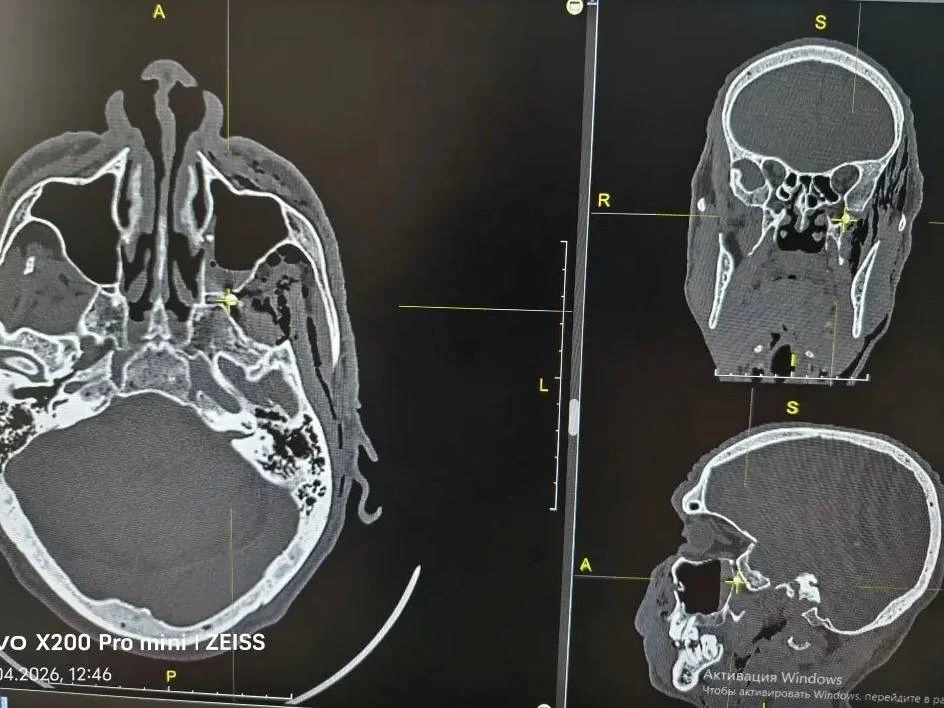

Пуля прошла через переднюю и заднюю стенки верхнечелюстной пазухи и остановилась в крыло-небной ямке — анатомическом центре, где проходят нервы и сосуды, рассказали в городской больнице Орска. Эта область соединяется с глазницей, полостью рта, носа, черепа и зоной под скулой.

Фото: Городская больница Орска